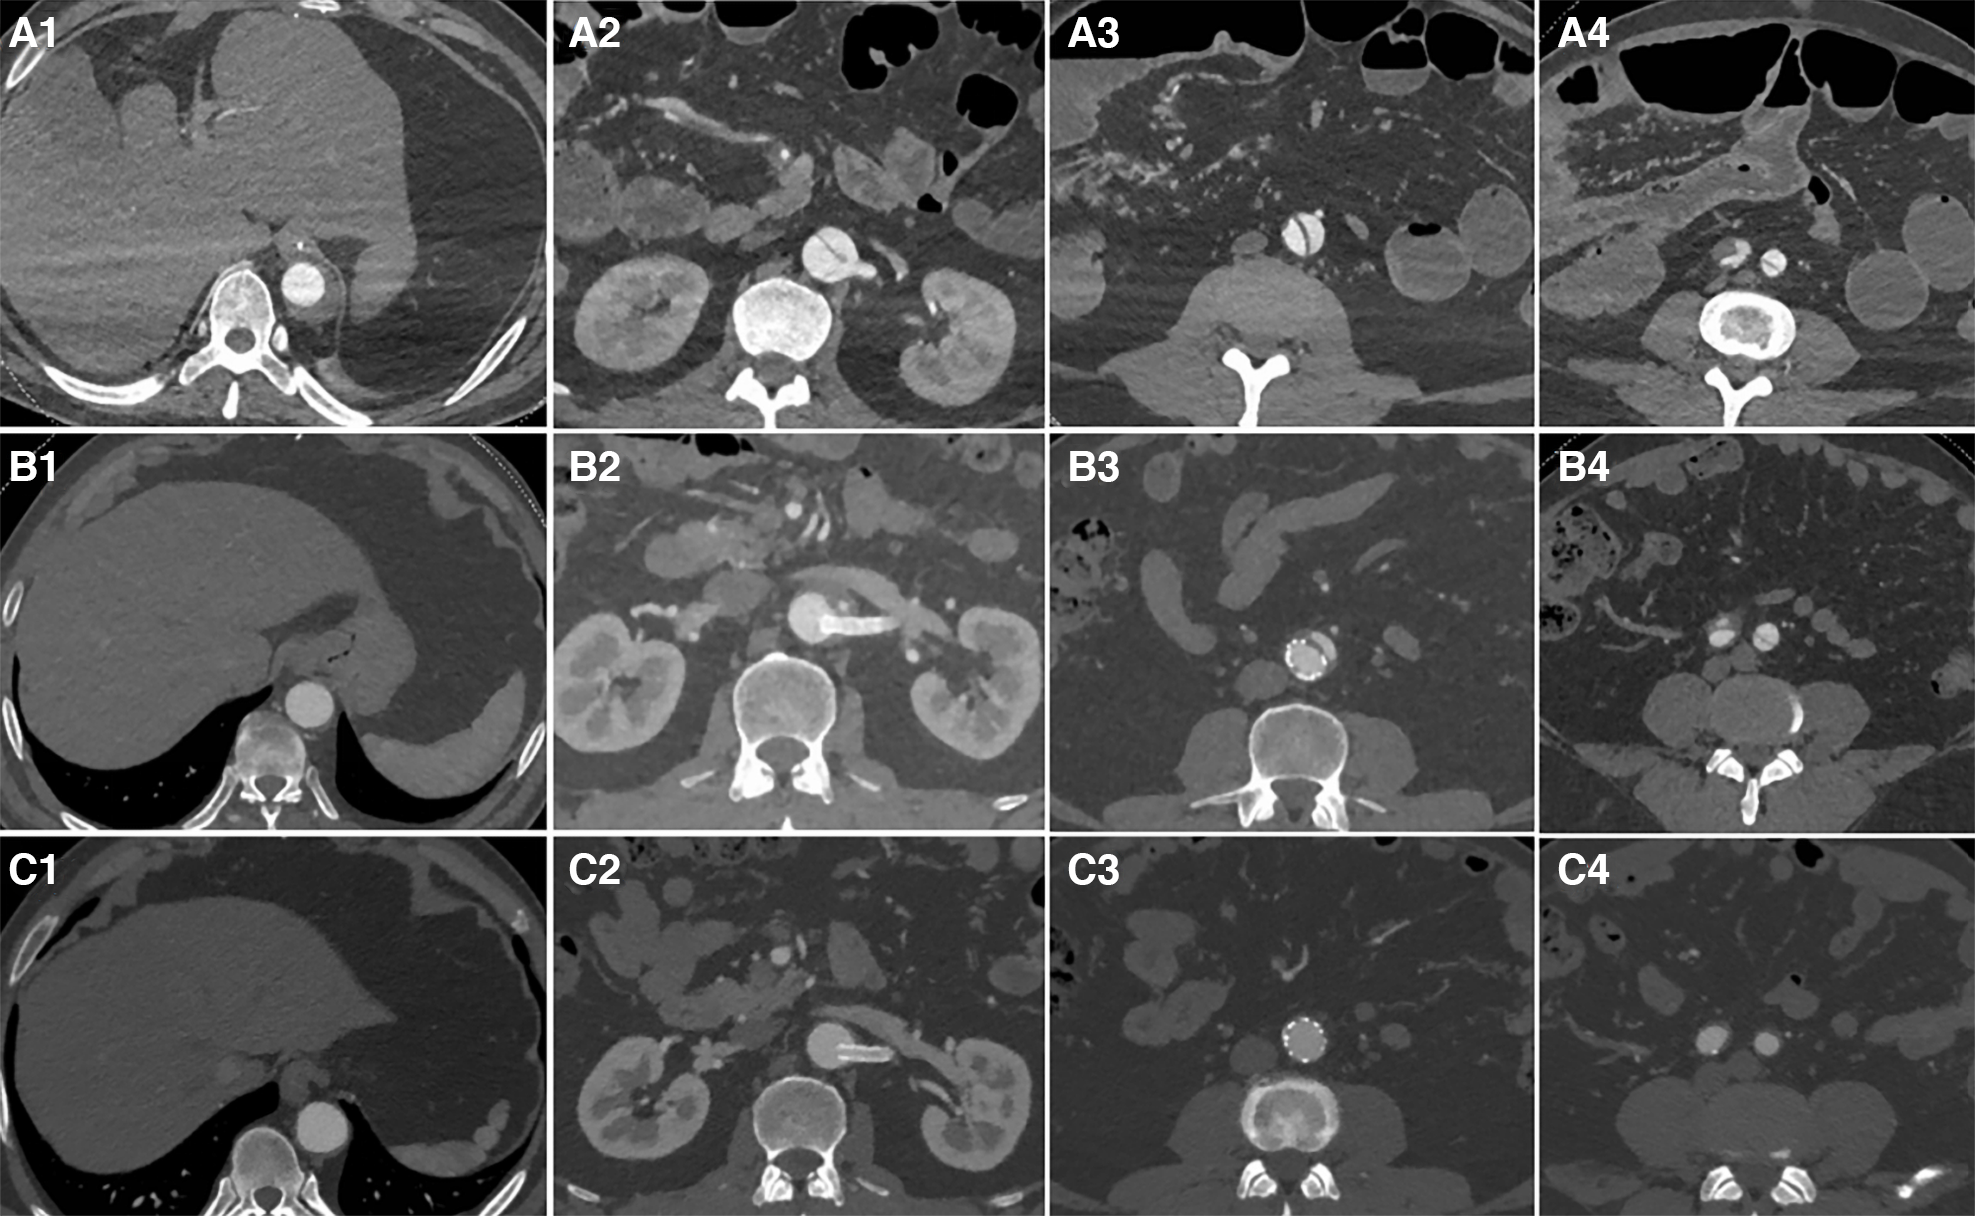

Third-stage surgery: Approximately three months after the second-stage surgery, aortic CTA was re-examined. Patients with thrombosis of the FL and no significant entry tear were followed up for an additional year (Figure 3). In cases where the FL was not completely thrombosed, often due to an entry tear in the iliac artery causing blood to flow back into the FL of the abdominal aorta, coils were placed from the iliac artery entry tear into the FL to promote thrombosis. Subsequently, a Fluency Plus stent graft was placed in the iliac artery to seal the re-entry. The average duration of the third-stage surgery was 32 ± 5 min.

Figure 3

The first row displays preoperative CT images, the second row presents CT images taken three months after the second-stage surgery, and the third row features follow-up CT images taken one year after the second-stage surgery. From left to right, the images respectively show sections of aortic dissection at the distal end plane of the primary stent, the renal artery level, 5 cm below the renal artery level, and 1 cm below the bifurcation of the iliac artery. After initial surgery, zones (A–D) exhibited a residual FL that had not fully thrombosed (A1-A4). Three months after the second-stage surgery, the aortic CTA revealed TL re-expansion without any obvious entry tears; follow-up observation was subsequently continued (B1-B4). One year after second-stage surgery, aortic CTA revealed that the FL had completely thrombosed and disappeared (C1-C4).